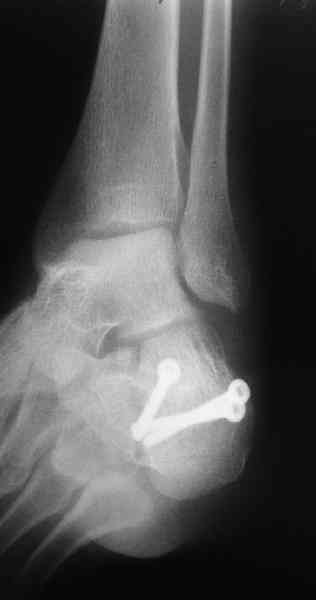

Re: Перелом пяточной кости

Открытый и закрытый способы лечения.